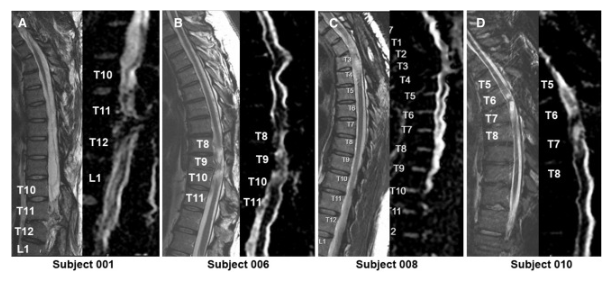

通過 MRI 和 DTI 成像評估動(dòng)態(tài)反應(yīng)

在 NSC 注射后,沒有放射學(xué)證據(jù)表明出現(xiàn)即時(shí)或延遲并發(fā)癥,包括術(shù)后即時(shí)或隨訪成像中沒有出現(xiàn)新的脊髓或軟組織水腫區(qū)域、增強(qiáng)或腫脹或積液。在純解剖或擴(kuò)散張量序列中均未觀察到脊髓脊髓軟化癥的可見形態(tài)變化。

在所有四名患者中,彌散張量成像 (DTI) 成像顯示在損傷部位和損傷部位的前端/尾部脊髓束外觀穩(wěn)定,但未顯示重塑或纖維束造影改善的廣泛證據(jù)。

MRI頸胸T2矢狀圖和AvDC矢狀圖